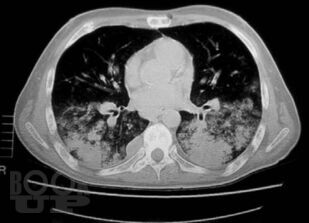

Книга профессора П.В. Власова посвящена современному состоянию лучевой диагностики заболеваний органов грудной полости. Она является первой в отечественной литературе крупной работой, в которой освещена диагностика заболеваний органов грудной полости: острых пневмоний и плеврита, хронических неспецифических заболеваний легких, туберкулеза органов дыхания, рака легкого, опухолей плевры, диффузных и диссеминированных процессов легких, опухолей и кист средостения. Все вопросы рассматриваются с учетом самых современных взглядов на патогенез и диагностику заболеваний.

Большим достоинством книги является комплексный подход к диагностике заболеваний. Наряду с традиционными методами ретгенологического исследования, такими как рентгенография и линейная томография, в книге получили полное освещение роль и место в современном комплексе диагностических средств такие методы, как компьютерная томография и ультрасонография, значительно расширившие возможности диагностики заболеваний.

Второе издание дополнено новым материалом, касающимся пневмоний, синдромов респираторной недостаточности и пневмокониозов, что заметно повысило его информативность и практическую значимость.